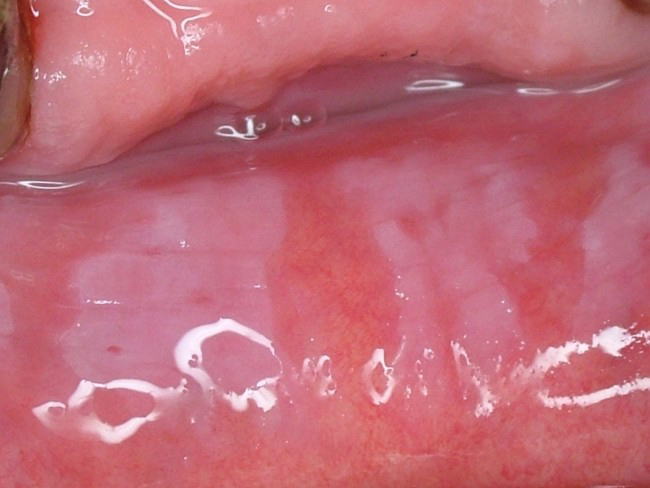

頬粘膜をはじめ口唇、舌、歯肉、口腔底粘膜などに発現する”摩擦によって除去できない”白斑病変。下の写真は口唇に発現した白板症(同一写真)です。口腔粘膜疾患としては比較的頻度が高く、単発で生じることも、また写真のように広範囲に生じることもあります。表面は粗いもの、丘陵上のもの、乳頭状のもの、また境界が限局性のもの、びまん性のものなど様々な病態を示します。状態によっては前癌病変としての性格を持つものもあります。

疼痛などの自覚症状は少ないのが普通です。

治療は原因除去(不適合な補綴物の刺激によって生じたものなど)、切除、レーザー照射などがありますが、原因や病態によって多様です。

鑑別診断を要するものとしては、扁平苔癬やカンジダ症などがあります。